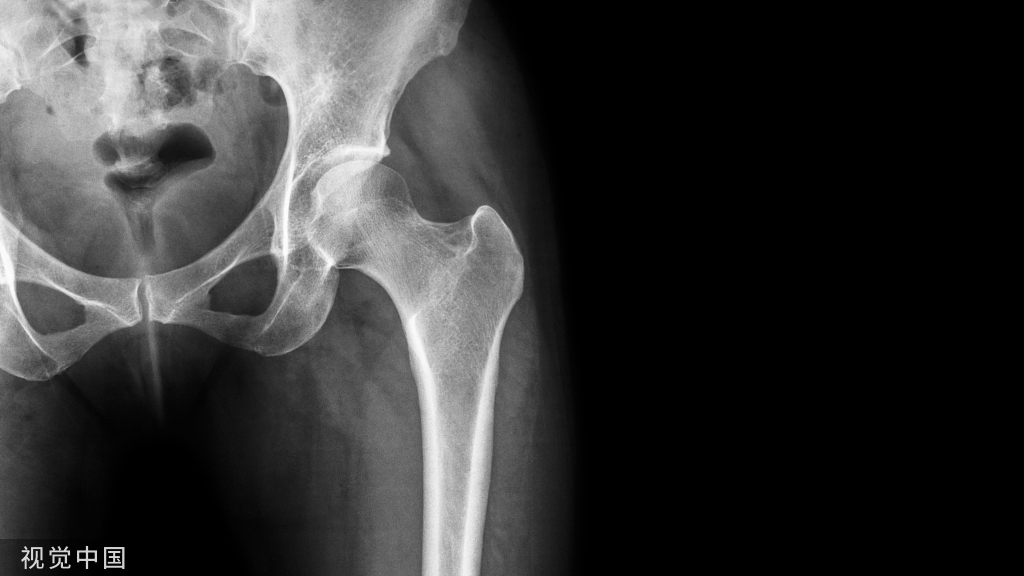

- 利用重建钢板进行预塑形,下方钉到坐骨上,上方钉到髂骨上,用钢板来重建后壁夹持住臼杯(图一)

图一

髋臼后壁缺失,无法稳定夹持臼杯,利用自体骨和钢板重建髋臼后上方及后壁